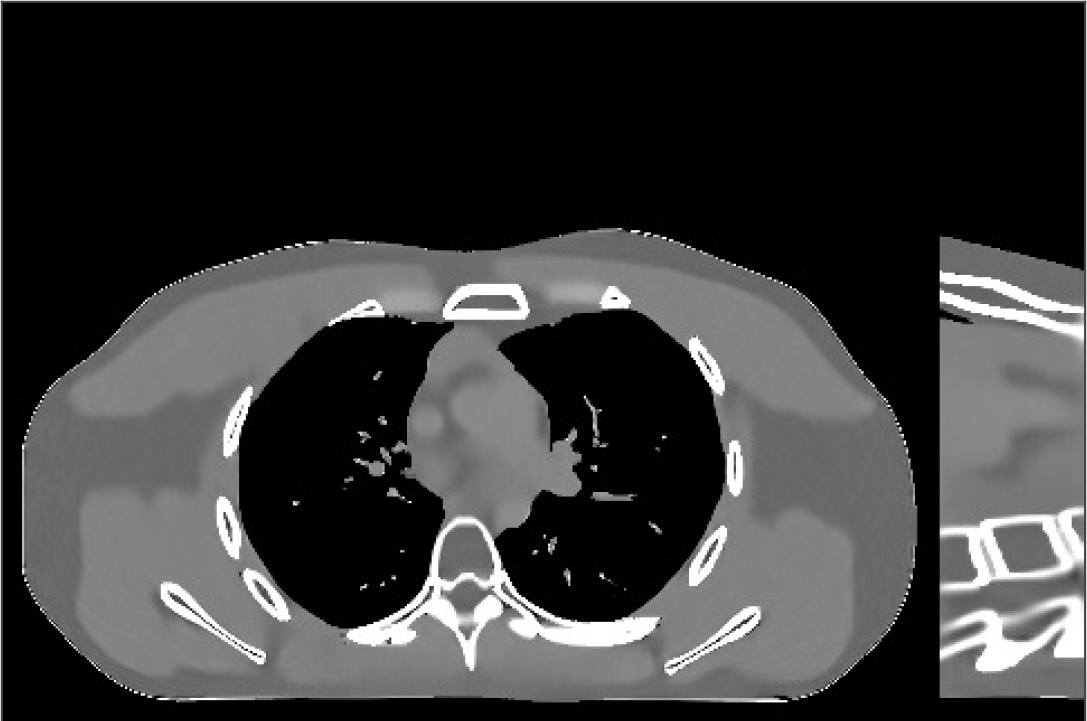

Fig.Β 7 shows the reconstructions (shown for the central axial plane in the 3D volume) for FDK (provided by GE Healthcare), PWLS-EP (corresponds to Fig.Β 8(a)), and PWLS-ULTRA with (corresponds to Fig.Β 9(a)). The PWLS-ULTRA reconstruction has lower artifacts and noise. Moreover, the image features and edges are better reconstructed by PWLS-ULTRA than by PWLS-EP or FDK.

Fig.Β 8 shows the reconstructions (shown for the central axial, sagittal, and coronal planes in the 3D volume) for PWLS-EP with different regularization strengths , denoted as a multiplicative factor of the parameter value in Fig.Β 7. Fig.Β 9 shows the reconstructions for PWLS-ULTRA (with patch-based weights) with different parameter combinations. For the sagittal and coronal planes, we show the central out of axial slices. Larger regularization strengths would achieve more noise reduction but simultaneously lower spatial resolution in PWLS-EP and PWLS-ULTRA, e.g., compare Fig.Β 8 and Figs.Β 9(a) and (d). Larger values of would achieve lower sparsities and more noise reduction but potentially oversmooth the image, e.g., compare Figs.Β 9(c) and (d). Small values of may introduce additional spurious noise in the PWLS-ULTRA reconstruction (compare Figs.Β 9(a) and (b)). Fig.Β 11 shows profiles of chest reconstructions (plotted from the central axial slice) for the PWLS-EP and PWLS-ULTRA methods. The profile locations are shown in green lines in Fig.Β 7. Both PWLS-EP with regularization strength X and PWLS-ULTRA (with patch-based weights) in Fig.Β 9(a) have lower noise than the PWLS-EP with regularization strength X. Though the spatial resolution of PWLS-EP with regularization strength X is close to PWLS-ULTRA in the selected soft-tissue regions, PWLS-ULTRA reconstructs bone and spine areas with higher resolution, and preserves small features better (compare the zoomed-in areas in Fig.Β 8 and Fig.Β 9).